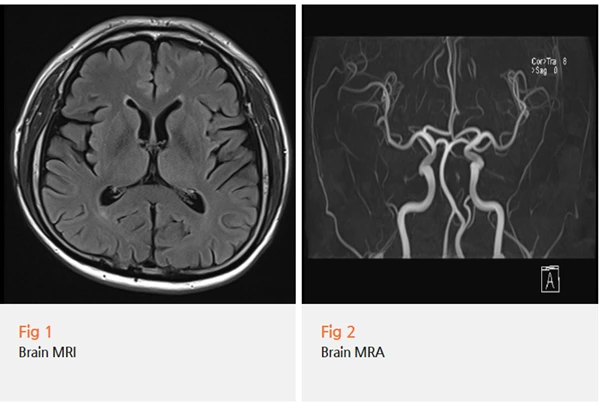

그래서 당일 뇌 MRI와 MRA 검사를 먼저 시행했어요.

결과는 다행히 뇌 내 기질적 병변 없음이었습니다.

뇌에서 나온 문제가 아니라는 게 확인됐으니, 다음으로 눈을 돌릴 곳이 생겼죠.